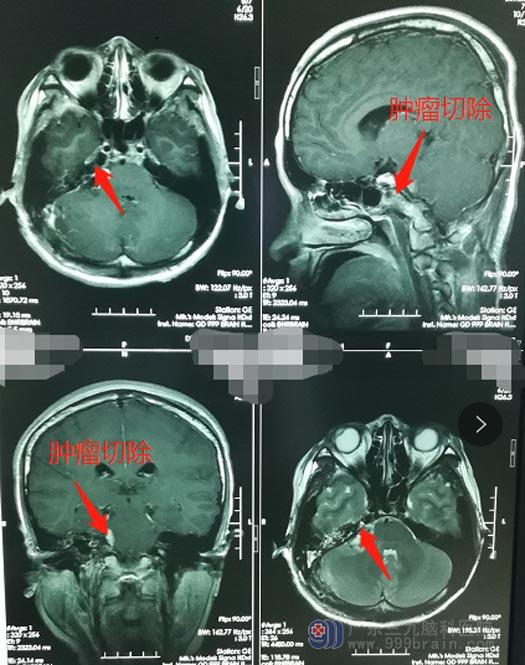

父母打消了顾虑,小珍也增强了战胜疾病的信心。充分的术前准备后,鲁明带领团队为小珍实施了“右侧桥小脑角区神经鞘瘤切除术”,在显微镜下分块切除肿瘤及大部瘤膜,肿瘤大小约3cm×3cm×3cm,上至三叉神经,下达末组颅神经,与面听神经及脑干明显粘连,内听道内的肿瘤也被完整切除,同时兼顾了对周边神经、血管解剖的保护,面听神经解剖保留。手术完成顺利。